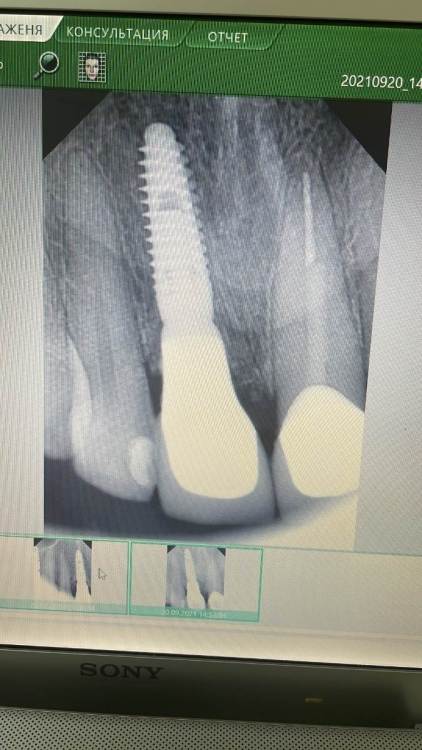

zubovolok Опубликовано 8 августа, 2023 Поделиться Опубликовано 8 августа, 2023 (изменено) Коллеги, приветствую. 2 года назад установил имплант (snucone) в позиции зуба 1.1, вестибулярно добавил био ос и резорбируемую мембрану, затем индивидуальный циркониевый абатмент на титановом основании и коронка на каркасе из диоксида циркония с нанесением. Три месяца назад пациент стал отмечать воспаление краевой десны м/у 1.2 и 1.1 - не кровит , ничего не выделяется, только внешне небольшой отек и гиперемия. Делали вектор - терапию 3 недели назад- не проходит . Метрогил- не помогает. Что это может быть ? Как исправить ситуацию? P.s - фиксация цементная. Снимки прилагаю- первый в день фиксации коронки в 2021 году , второй на сегодняшний день.Фото состояния десны нет. Изменено 8 августа, 2023 пользователем zubovolok Ссылка на комментарий

Aquarius Опубликовано 8 августа, 2023 Поделиться Опубликовано 8 августа, 2023 (изменено) Приветствую. -Контактный пункт ослаблен - Невидимый фрагмент цемента вестибуло-орально - Раскручен винт абатмента-микроподвижность-подтекание - Графт секвестрирует потихоньку Цифры глубины зондирования бы узнать Если прям совсем позанудствовать, то между 11,12 вроде цемент виден Изменено 8 августа, 2023 пользователем Aquarius Ссылка на комментарий